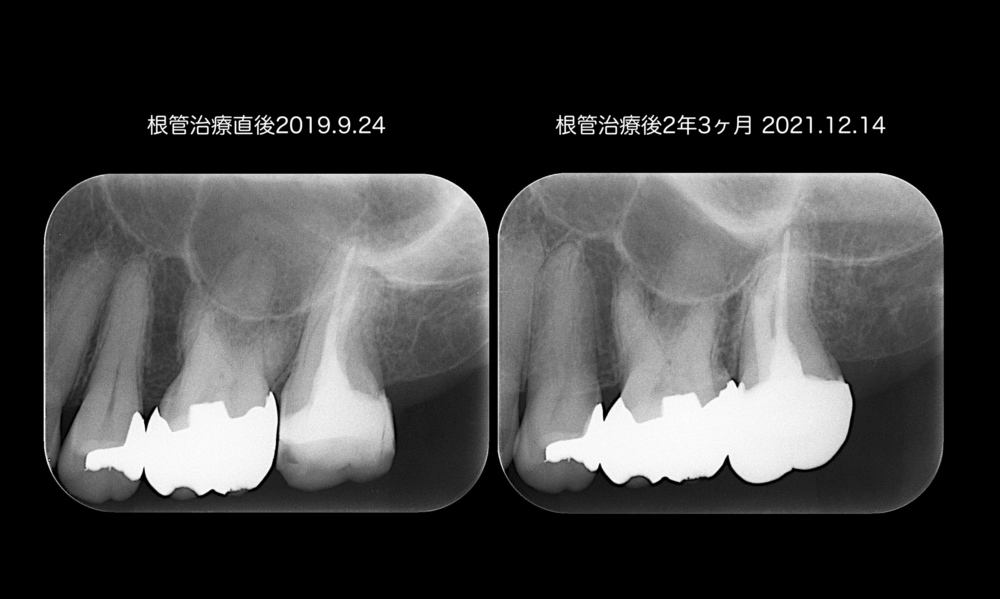

根管治療後の経過

患者さんは、治療後『アイスを食べた時の痛み』はなくなりました。

根管治療後2年程度までは経過良好です。